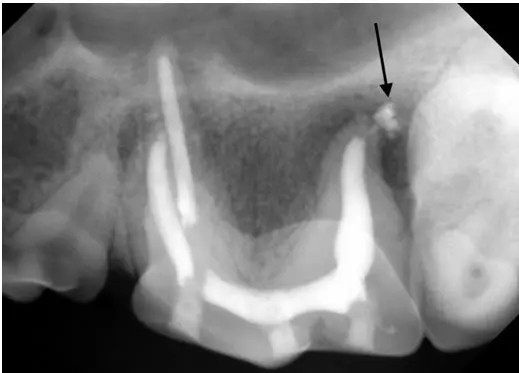

Why does this happen? When a tooth becomes non-vital (dies), whether or not they are infected, the necrotic pulp tissue begins to break down inside the tooth. Some of this material begins to leak out around the apex of the root through the small apical delta canals that extend from the end of the root canal to the outside of the root. If you look below at the final X-ray from the past newsletter, you can see the cement highlighting some of those canals, leading to the puff of cement (arrow) on the X-ray. As these materials leak outside the root, they elicit an inflammatory response in the periapical tissues. The presence of bacteria hastens this process. The end result is demineralization of the bone secondary to chronic inflammation.

Final X-ray after root canal therapy. Some faint white lines of cement can be seen leading from the filling material inside the root to the cement “puff” indicated by the arrow.